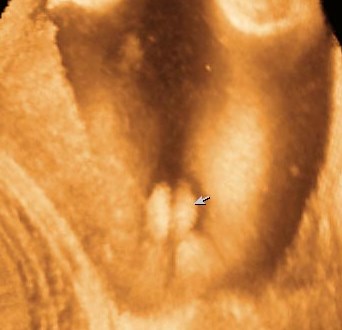

Пол малышаЗавтра идем к ней на УЗИ для точного определения пола ребенка.Хочу чтобы было точно видно так

Или

Так

У меня ребенок когда делали 2д, показал себя так:

Как только включили 3д запись, он решил дубасить ногами мамин живот и получилось вот так: